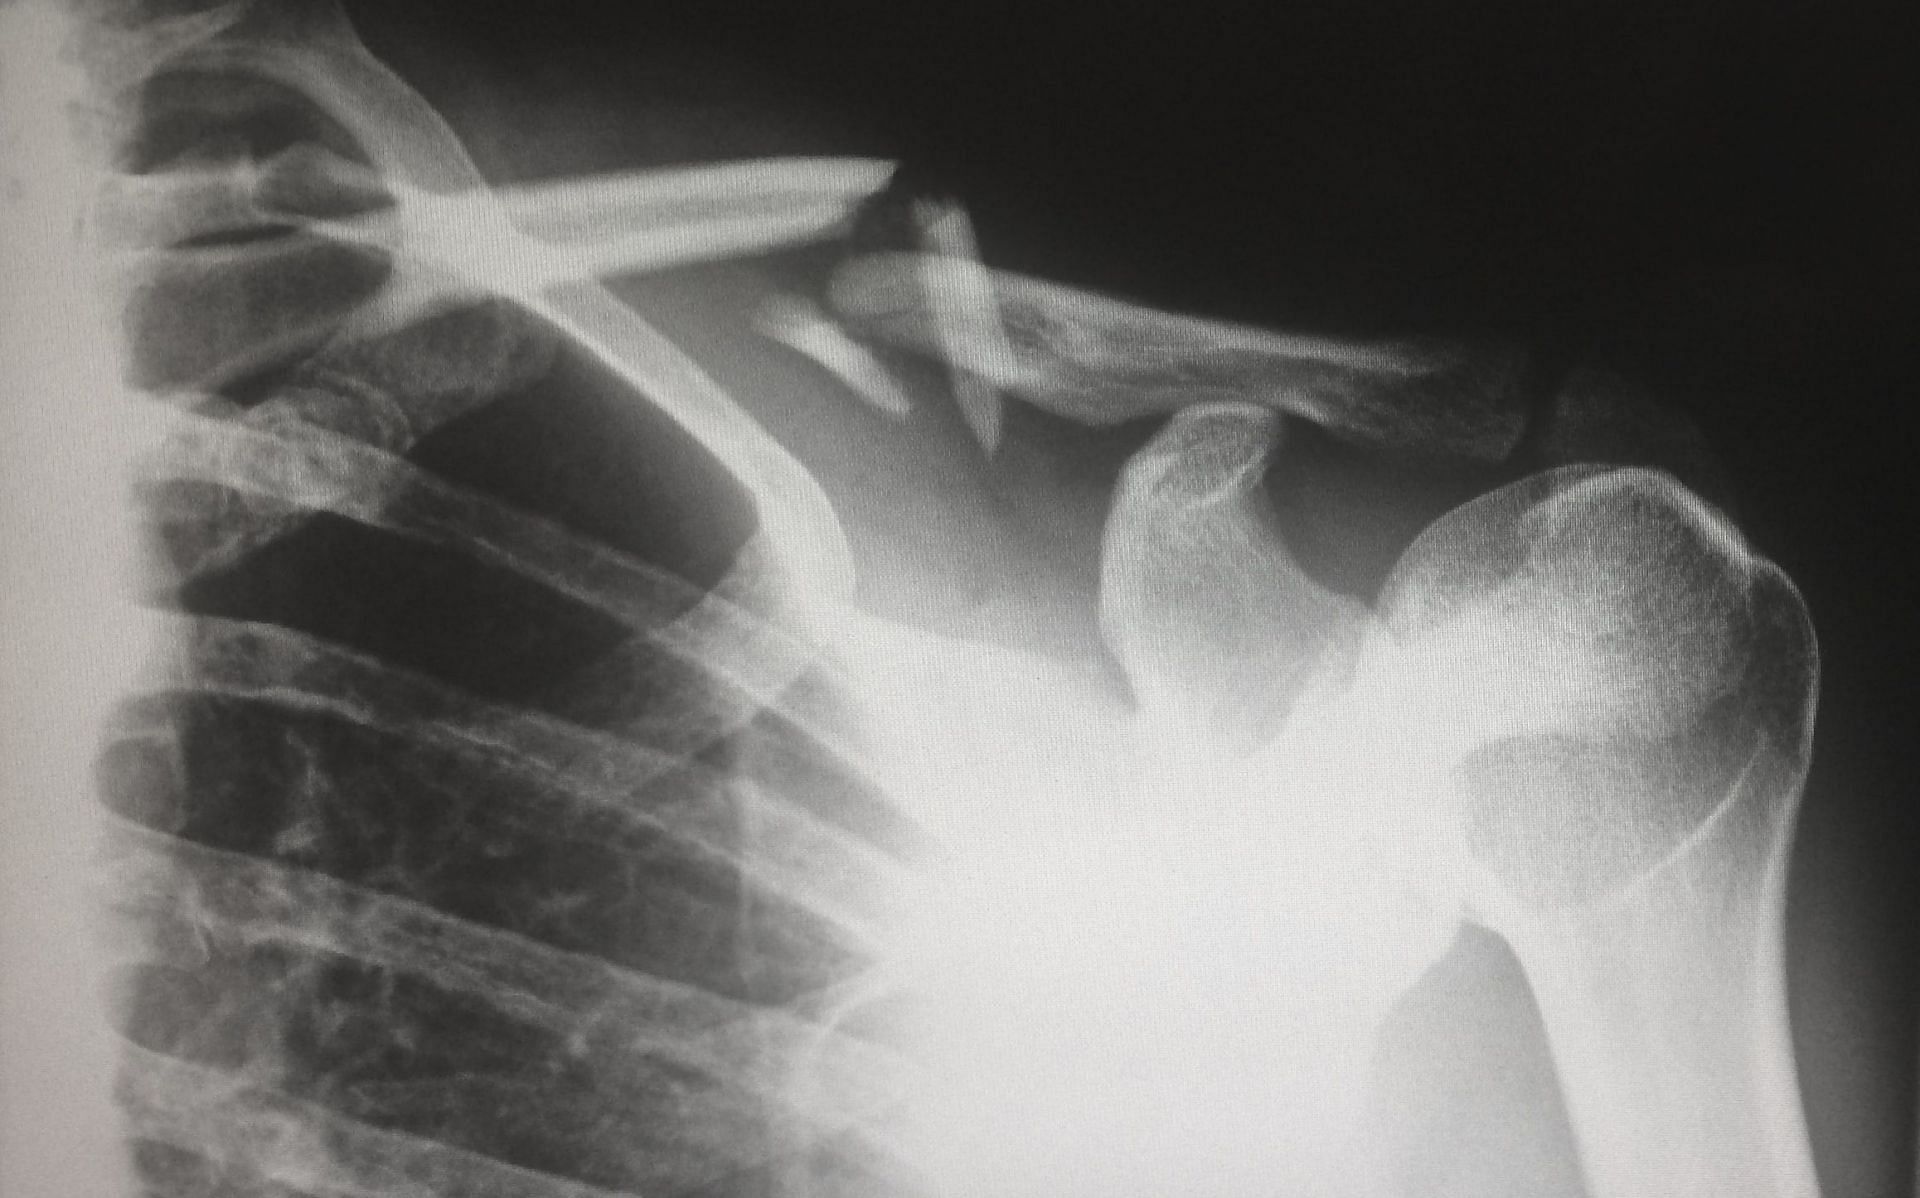

Adam Cole suffered shoulder labrum tears and has reportedly opted not to have surgery. In the latest Wrestling Observer Newsletter, it was reported that Cole decided to undergo physical therapy on his shoulder instead of invasive surgical procedures.

Specialized cartilage tissue in the shoulder is known as the labrum, and injuries can cause pain and instability in the shoulder. The labrum is a cup-shaped rim of cartilage that supports the ball-and-socket joint of the shoulder.

The shoulder joint is composed of the glenoid (socket) and the head of the upper arm bone, also known as the humerus (ball). The labrum helps with shoulder stability and, when torn, can lead to partial or complete shoulder dislocation. Shoulder anatomy is quite complex and athletes often get injured in such events.